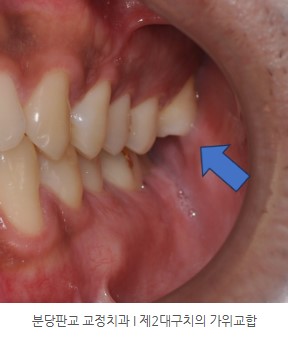

좌측 제2대구치의 가위교합(scissors bite)

가위교합이란 상하악치아가 교두-와 교합을 하지 않고, 어긋나 물리는 관계입니다.